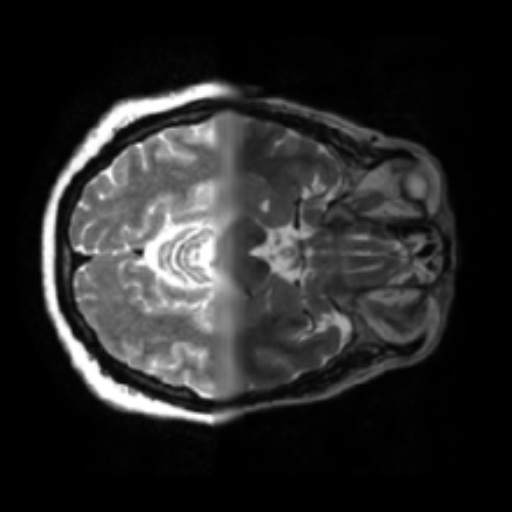

- 1.2 Examples of homogeneity in medical imaging modalities illustrating the similarity of the underlying subject (PET, CT, and MRI).

- (c) MRI of the brain1111footnotemark: 11

Thirdly, while seeming counter to the second point, while in a broad sense medical images are heterogeneous due to the very different imaging techniques and separation based on medical specializations (head scans vs foot scans), within a given data type, there is very high visual similarity. For example, all chest X-rays will look very similar due to standardized acquisition methods and tools, but also in large part, due to the high homogeneity of the human biology, see figure 1.2. For the chest scan example, most human bones and organs will have almost identical structures, similar sizes, and composition. Furthermore, the way these scans are collected is standardized, so the patients will all be positioned at the same angle and distance from the imaging machines. This is true even for data samples that have completely different labels, as the characteristics that indicate one diagnosis or another are often identified by very small, granular differences, which are visually very small in absolute terms. This poses a challenge to researchers in the sense that they can’t directly adapt many of the more recent and best-performing classes of Self-Supervised methods, such as contrastive learning. This has allowed us to develop methods that are tailored specifically for medical images.